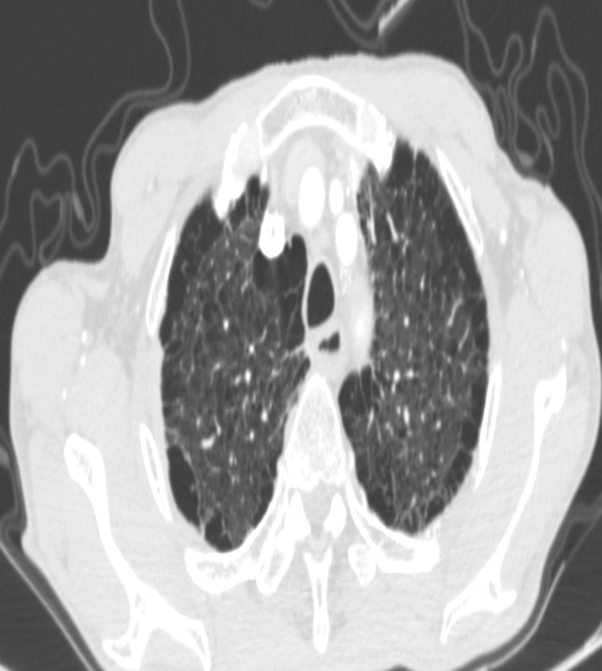

患者 75 岁高龄,慢支肺气肿及双肺广泛肺大疱,肺功能欠佳,经过精心的术前准备以及全院多学科讨论制定了详细的手术和围手术期治疗方案后,夏少锋主任团队在小年前一天给程老安排了手术。